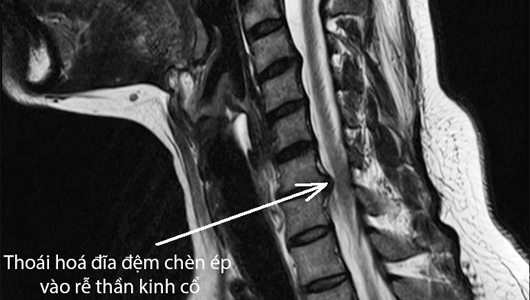

Bệnh đau cổ vai gáy khá phổ biến, có thể do nhiều nguyên nhân khác nhau như: nguyên nhân hay gặp nhất do căng cơ sau chơi thể thao, sai tư thế, thoái hóa, thoát vị đĩa đệm các đốt sống cổ, trong 1 vài trường hợp có thể là dấu hiệu của nhồi máu cơ tim, u đỉnh phổi... Bệnh thường xuất hiện sáng sớm lúc ngủ dậy hoặc sau khi lao động nặng hoặc bị nhiễm lạnh. Bệnh sẽ tăng khi đứng, đi, ngồi lâu hoặc ho, hắt hơi, vận động cột sống cổ, khi thời tiết thay đổi; bệnh sẽ thuyên giảm khi nghỉ ngơi.

- Những đối tượng bị tác động từ bên ngoài, các tác động bệnh lý bên trong cơ thể như những người bị thoái hóa đốt sống cổ, thoát vị đĩa đệm, lao, ung thư vùng cổ cũng là nguyên nhân trực tiếp gây ra đau mỏi vai gáy triền miên cho người bệnh.